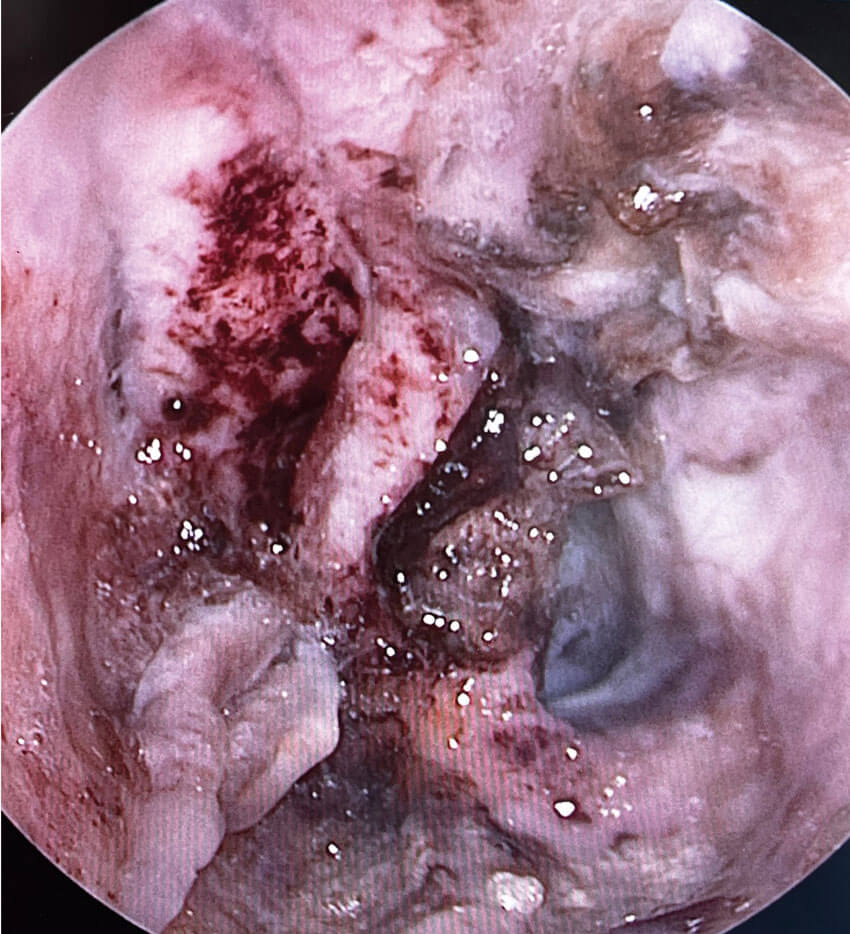

Chronic laryngitis is a condition where prolonged inflammation caused by the aforementioned factors leads to tissue changes, swelling, hyperaemia and minor tissue damage in the mucous membrane. Irritants and inflammation disrupt the delicate balance of the microbial flora, also known as microbiome, resulting in a narrowed microbial diversity. Microbial diversity is an important factor in resistance, and limited diversity may allow pathogen proliferation, leading to chronic purulent inflammation, such as laryngitis sicca. Based on clinical experience, laryngitis is rarely associated with bacterial infection. However, in laryngitis sicca, pathogenic bacteria, fungi, or their combinations can form biofilm colonies that are highly resistant to antimicrobial treatment and local immunity [3].

Prolonged exposure to irritants, particularly tobacco smoke, is considered a cause of dysplastic changes such as laryngeal leukoplakia that possess 2–20% risk of malignant transformation. Recent studies have shown a pathway leading from microbiome changes and chronic biofilm infections to dysplasia [4].